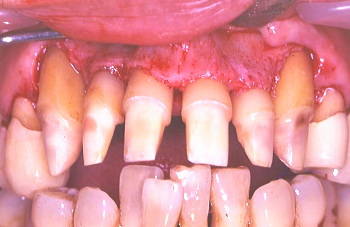

⑥ 骨が異常に減退しているので歯冠が長く見える。また歯の根っこの表面に歯石が見られ、これが存在する限り、歯周病はよくならないのでこれを取り除くのも一つの大きな外科の目的である。○印で示しているのは歯周ポケットの中で歯根面に付着していた歯石である。

⑦ この写真でも骨が異常に減退した長い歯冠とその歯の根っこの表面に歯石が見られる。○印で示しているのは歯周ポケットの中で歯根面に付着している歯石。

⑧ 歯根に付着していた歯石を除去した。もう一つの大きな外科手術の目的は歯周骨が細菌作用により、デコボコになった骨の表面部分を滑らかに整える事である。

⑨ 歯周外科により、歯根面全体と骨表面がきれいに清掃、整えられた。